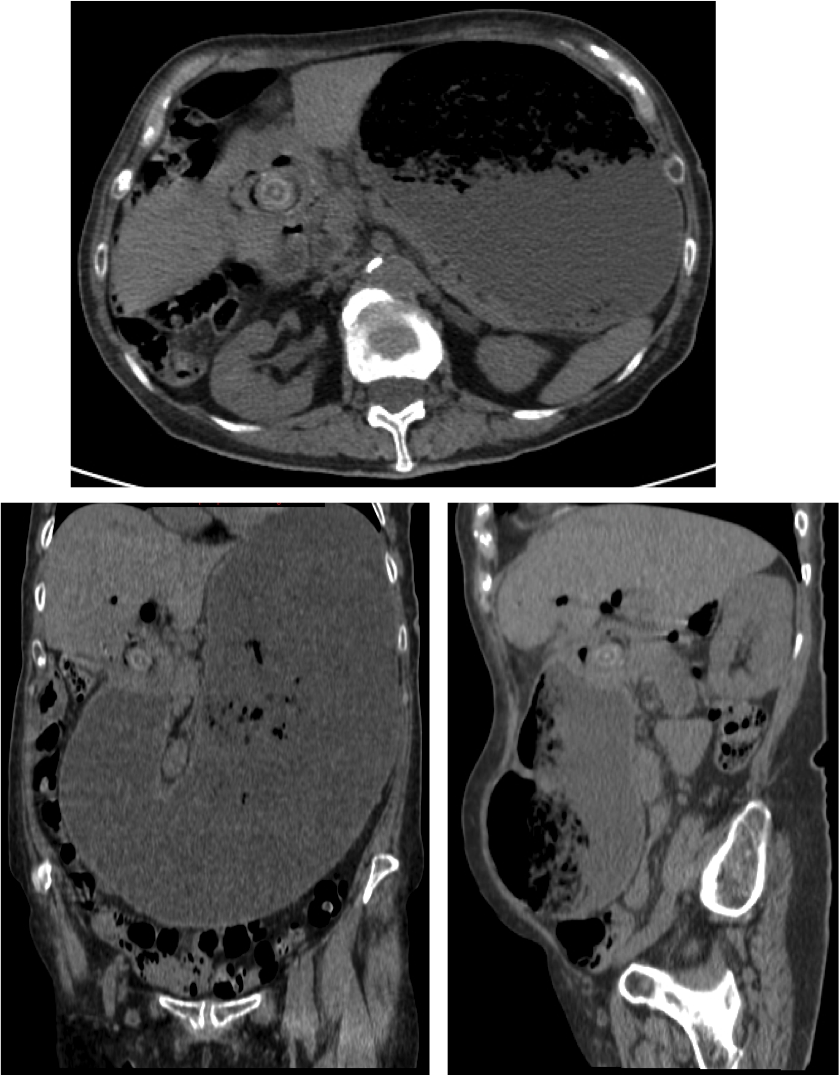

Triada de Rigler:

Otro caso: 1) Neumobilia + Dilatación de la cámara gástrica 2) Litiasis bilar + vesícula con proceso inflamatorio 3) Fístula vesiculo entérica 4) Dilatación de la cámara gástrica por obstrucción.